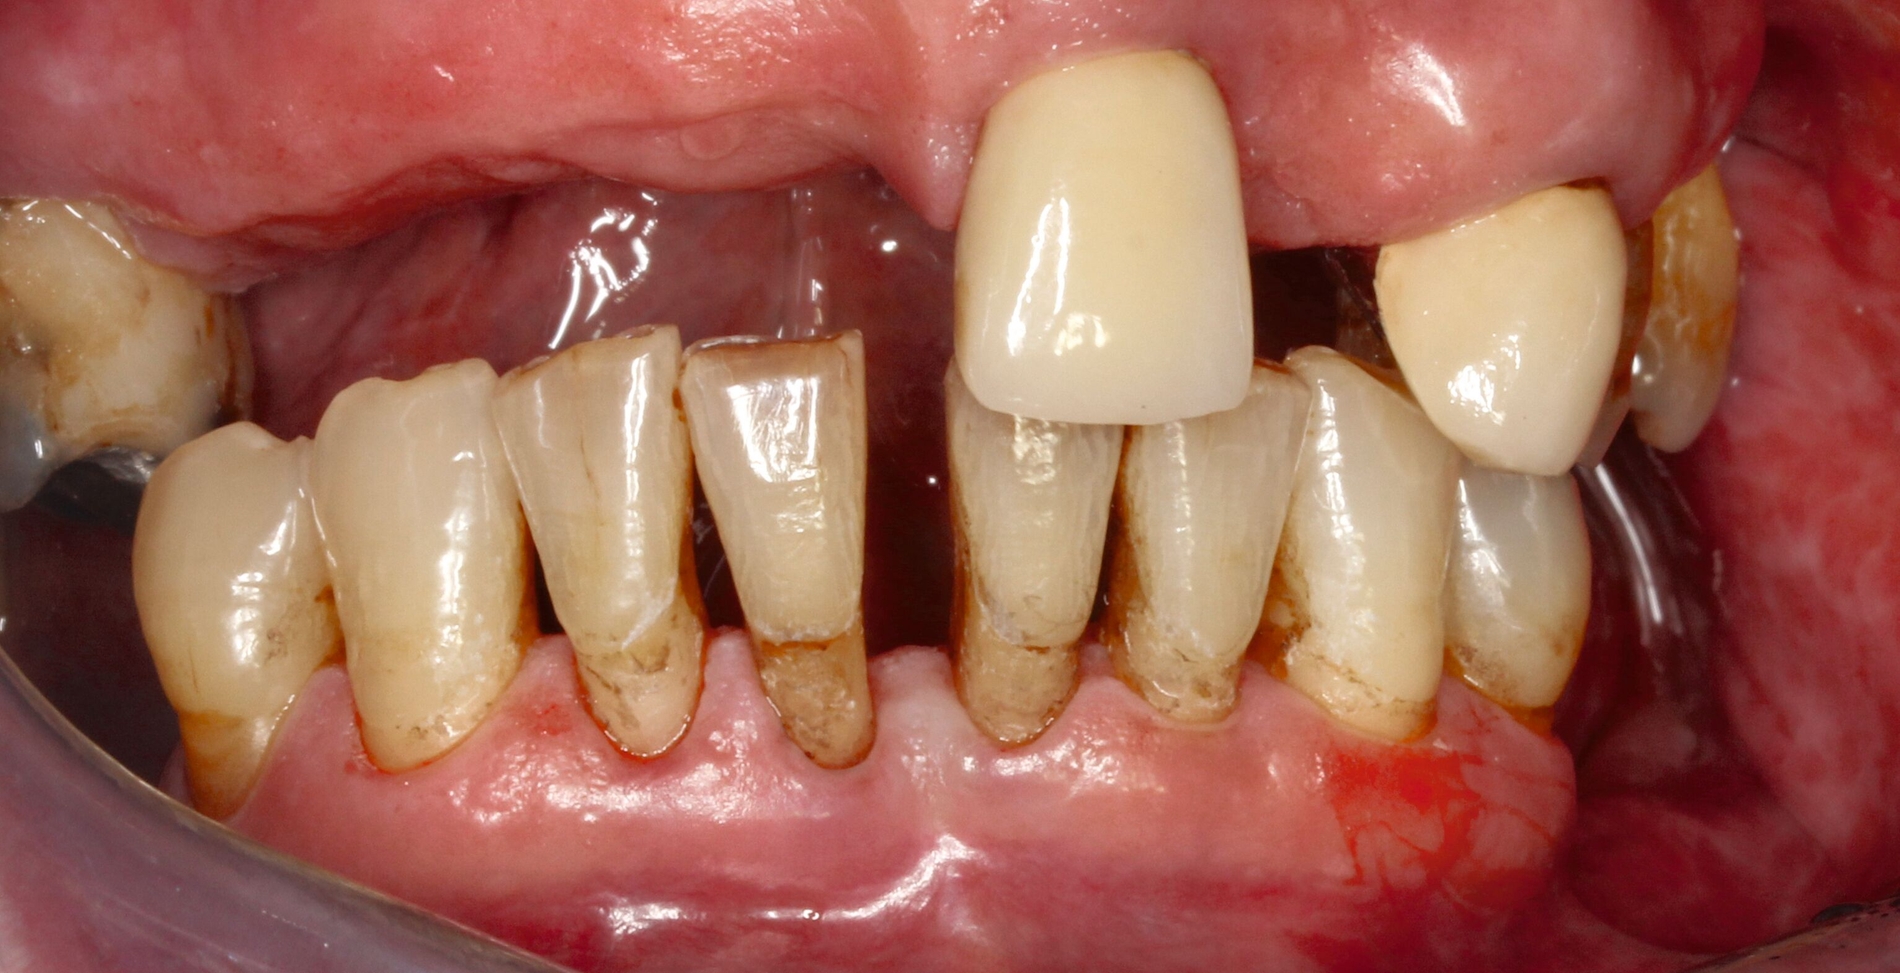

Ist die Läsion aktiv oder inaktiv? Die Beantwortung dieser Frage ist die Ausgangsbedingung für den Therapieentscheid. Wenngleich die Unterscheidung nicht immer einfach ist, ist eine weiche Textur bei Sondieren und eine deutliche Plaquebedeckung ein sicheres Zeichen für Kariesaktivität [Carvalho und Lussi, 2017]. Bei aktiven Läsionen sollten Lokalisation und Ausdehnung genau exploriert werden, was die Behandlungsoptionen wesentlich bestimmt (Abbildung 1). Bei inaktiven Läsionen ist keine restaurative Therapie erforderlich, jedoch sind risikoadaptierte Präventionsmaßnahmen angezeigt.

Eine bekannte Nebenwirkung bei Anwendung auf kariösen Läsionen ist die Schwarzfärbung des behandelten Bereichs (Abbildungen 3, 4). Verfärbungen können aber auch bei Applikation auf kariesfreien Wurzeloberflächen entstehen, diese sind jedoch mit einer professionellen Zahnreinigung gut zu entfernen (Abbildung 2).

Tatsächlich zeigt die klinische Erfahrung, dass es möglich ist, bei mehrmaliger Applikation innerhalb eines Vierteljahrs auch sehr aktive Läsionen mit taktil weicher Oberfläche trotz eingeschränkter Mundhygiene gut zu erhärten (Abbildung 4). Für die koronale Karies bei Kindern konnte die bessere Wirkung nach wiederholter Anwendung allerdings nicht bestätigt werden. [Smutkeeree et al., 2025].